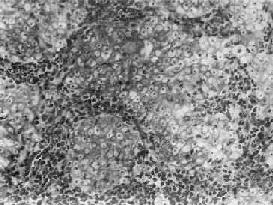

鼻咽泡状核细胞癌

图9-6 鼻咽泡状核细胞癌

癌细胞境界不清,呈合体状,核大圆形,染色质少,呈空泡状,含1~2个肥大的核仁,癌细胞间有淋巴细胞浸润